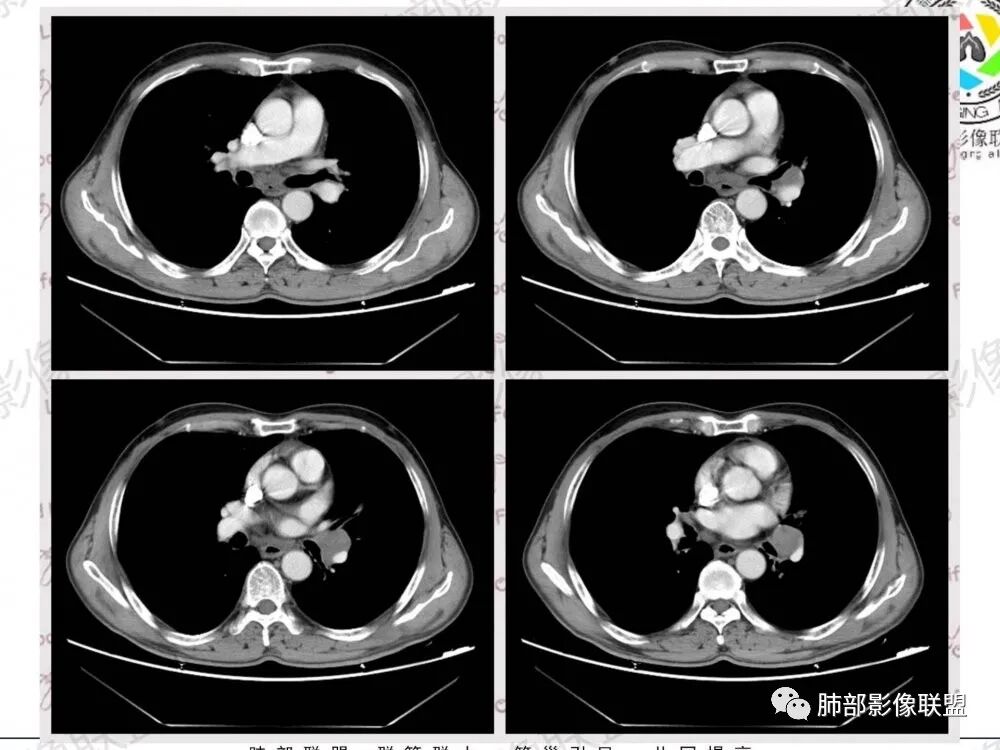

再见理想:

中纵隔及左肺门肿大淋巴结,局部有融合趋势,周围血管受压表现,轻度较均匀强化,肺内除了气肿和左肺尖陈旧病变没发现特殊异常,淋巴瘤?别的想不到了。

57岁男性,长期吸烟史,有血吸虫病史,有粉尘接触史。发现纵隔淋巴结肿大2年,声嘶伴咳嗽咳痰半月。两年前胸部CT见左上肺尖后段结节并肺门淋巴结肿大,治疗后左上肺结节消失。目前胸部CT:肺气肿,左上肺尖后段见条索影(原来结节治疗后的改变?),肺门、纵隔淋巴结肿大并融合,似见薄壁包膜样强化。考虑淋巴结结核可能性大,注意鉴别淋巴瘤、转移、结节病等。

男性,57岁,发现纵膈淋巴结肿大,现声嘶伴咳嗽咳痰。COPD背景,纵隔内、左肺门多发肿大淋巴结相互融合,冰冻纵隔?增强后轻度强化,主气管向右侧推移。考虑肺癌,小。

影像特点:

1.左肺门及纵隔见异常增大淋巴结,部分融合,不均匀轻度强化,未见明显坏死。

肿大淋巴结与纵隔血管等结构“无缝”贴合。

2.纵隔增宽但依旧居中。

点评:

1.这应当是常见的小细胞肺癌的转移方式。

别忘了,患者左肺上叶那个略显饱满的的小结节,有理由相信那是发源地。

因为这些符合肺癌的整个转移路径!